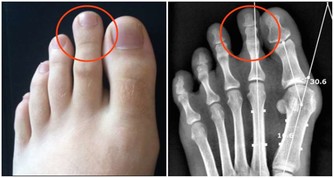

在人類種係發生和演化過程中,食物種類的日趨精細,帶來了咀嚼器官的退化,造成頜骨長度與牙列所需長度的不協調,結果是頜骨慢慢退化,逐漸縮小,而牙齒本身的大小並沒有改變。但是,智齒是牙列中最後萌出的牙齒,當智齒萌出時,往往因為萌出位置不足,導致程度不同的阻生。

智齒及智齒萌出過程中,牙冠可部分或全部為齦瓣覆蓋,齦瓣與牙冠之間形成較深的盲袋,食物及細菌極易嵌塞於盲袋內;加之冠部牙齦常因咀嚼食物而損傷,容易形成潰瘍。